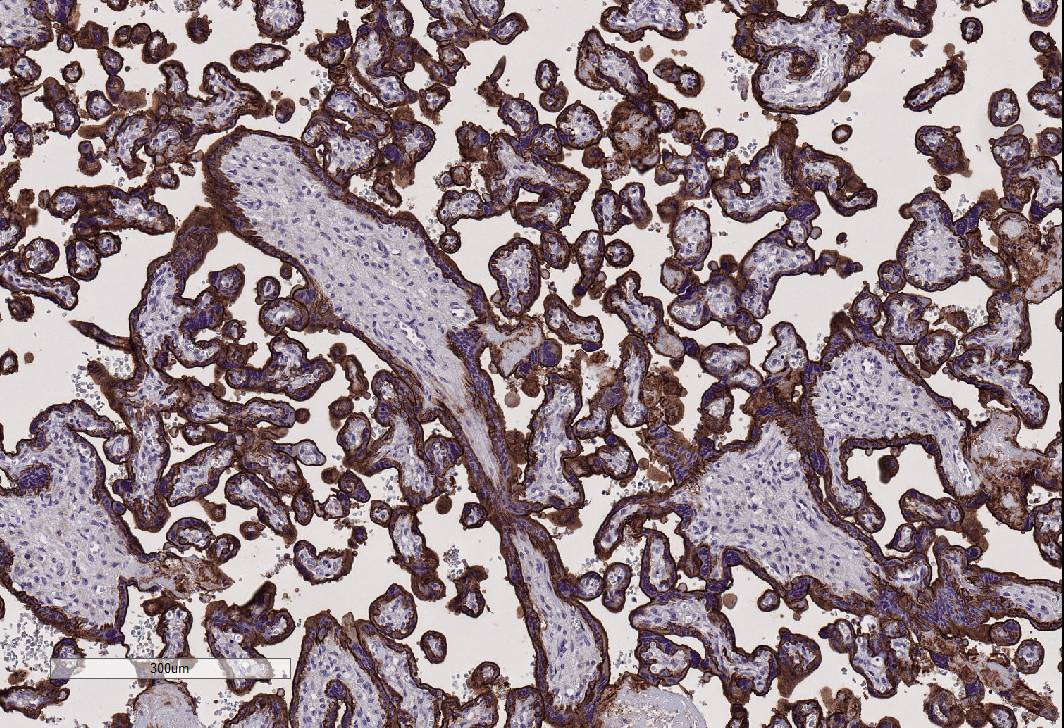

Unlike other antibody assays, IHC allows researchers to visualize exactly where proteins are localized within tissues (specific cell types and subcellular localization; cell membrane, cytoplasm or nuclear).

- Endothelial cell markers, such as CD31, can be used to evaluate tumor angiogenesis.